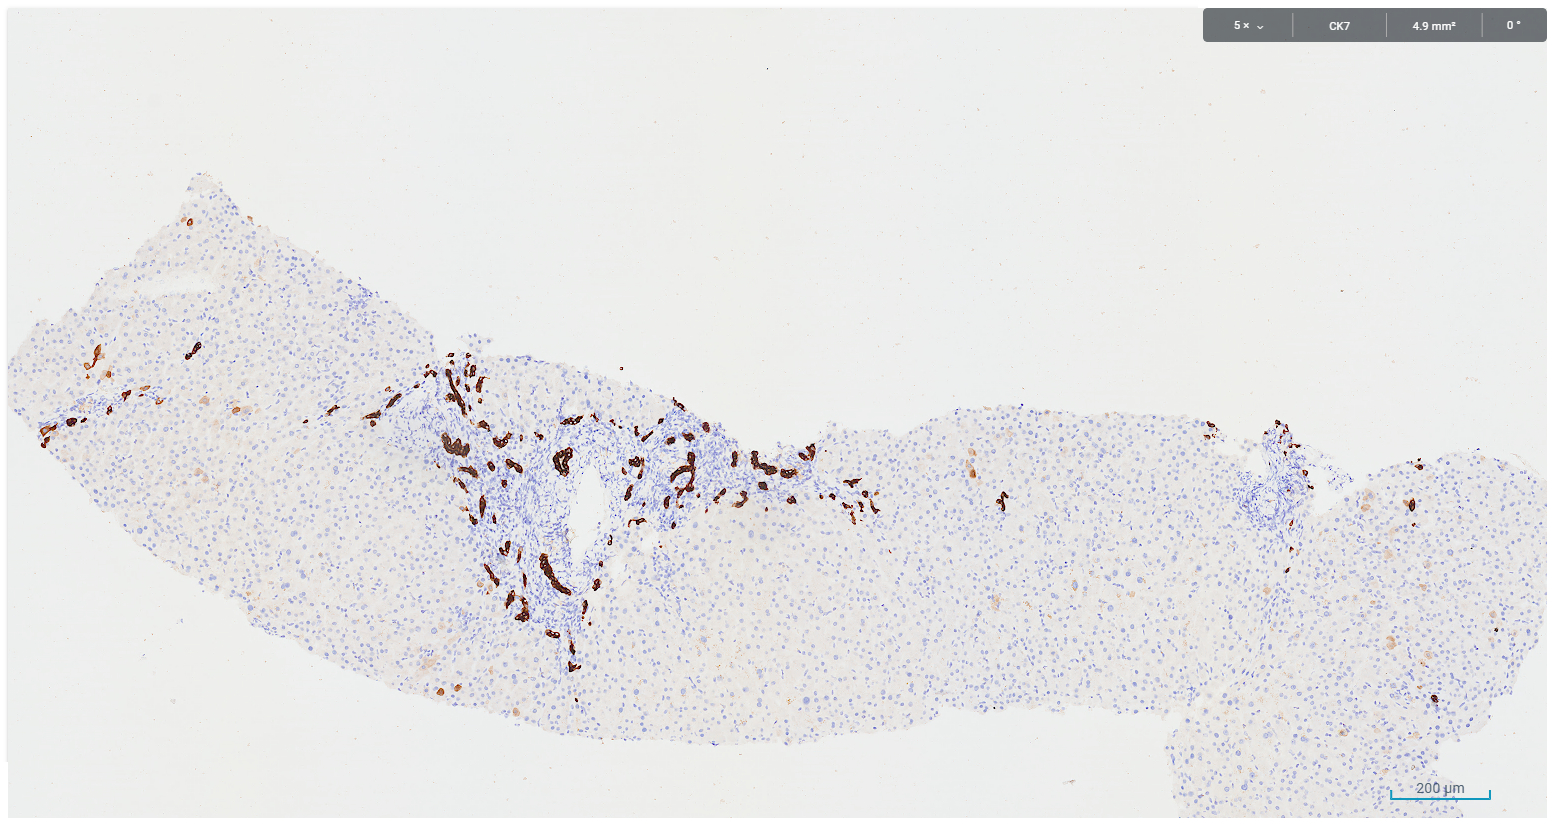

A core biopsy taken from the right hepatic lobe showed periportal chronic inflammation without a prominent plasma cell component, and focal interface activity (Figure 1). Mild bile ductular proliferation and mild periportal fibrosis were noted and highlighted with CK7 immunohistochemistry (Figures 2 and 3). There was no evidence of bile duct injury or ductopenia. The hepatic lobules contained scattered chronic inflammatory infiltrate and mild canalicular cholestasis (Figures 4 and 5). Steatosis, confluent necrosis, Mallory-Denk bodies and granulomata were not identified.

Figure 3. legend: CK7 immunohistochemistry highlights bile ductular reaction at the corresponding site of figure 2